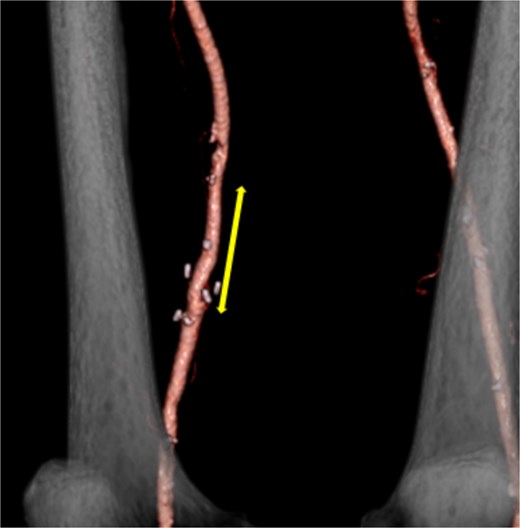

On pathological examination, the resected aneurysm wall revealed no findings other than atherosclerotic changes. Postoperative lower extremity edema was not observed despite using the FV as a graft. Postoperative CT showed no evidence of complications at the reconstructed vascular site (Fig. 2). Postoperatively, the patient was initiated on warfarin therapy. No aneurysm or pseudoaneurysm formation was observed at the reconstructed site on follow-up CT 3 years postoperatively.

Postoperative contrast-enhanced CT revealed no aneurysm or stenosis formation at the reconstructed site (arrow) and optimal visualization of distal vessels.